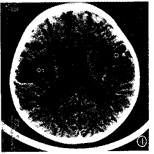

图4 脑软化和脑萎缩:大脑沟普遍性增宽加深,侧脑室扩大 ,双颞叶脑软化灶。

3~6个月内复查CT 18例,CT表现异常9例,EH 3例,PVL 6例,其中脑软化和脑萎缩1例 。6个月~1岁内复查CT 7例,CT表现异常4例,均为PVL,其中基底节区、放射冠区点状钙化 各1例,脑软化1例。1~2岁内复查CT 10例,CT表现异常7例,PVL 5例,脑萎缩1例,CT表 现为:整个大脑沟普遍性增宽加深,可伴小脑沟加深,大脑半球间裂多正常或整个增宽,脑 室多扩大,且较显著。脑软化和脑萎缩1例(图4)。4岁内复查CT 2例,CT表现异常1例,为P VL。